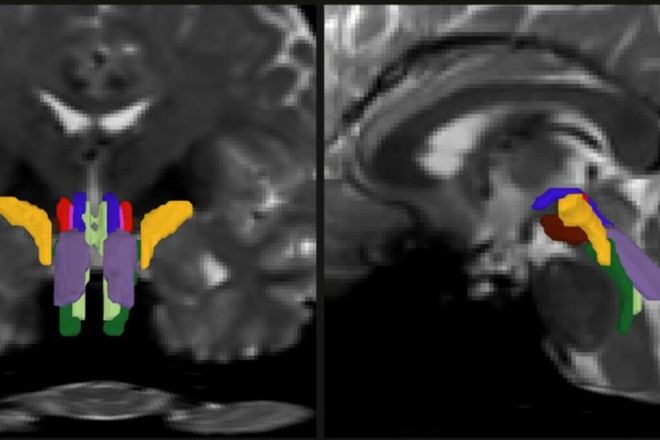

La resonancia magnética por difusión permite trazar las largas ramas o "axones" que los neuronas utilizan para comunicarse. Estos axones están recubiertos por una vaina grasa llamada mielina, lo que complica aún más su visualización debido a su pequeño tamaño y a las interferencias causadas por fluidos cerebrales y movimientos corporales. Para superar estos obstáculos, Olchanyi desarrolló BSBT, que crea un “mapa probabilístico” al trazar los haces desde áreas adyacentes del cerebro hacia el tronco encefálico.

A través del entrenamiento del algoritmo utilizando 30 escaneos en vivo del proyecto Human Connectome Project (HCP), Olchanyi logró capacitar a una red neuronal convolucional para identificar correctamente estos haces. Las pruebas realizadas demostraron que BSBT podía reconocer consistentemente los mismos haces en escaneos separados realizados con dos meses de diferencia.